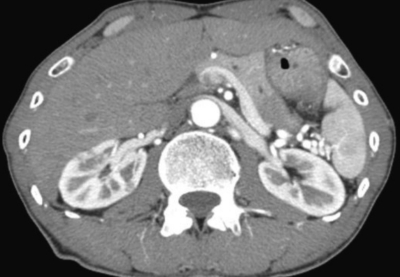

血液所見:赤血球 423 万、Hb 12.9 g/dL、Ht 37 %、白血球 6,400、血小板 21 万。血液生化学所見:尿素窒素 13 mg/dL、クレアチニン 0.5 mg/dL、総蛋白 8.5 g/dL、アルブミン 3.9 g/dL、IgG 3,305 mg/dL (基準 960〜1,960)、IgA 159 mg/dL (基準 110〜410)、IgM 67 mg/dL (基準 65〜350)、IgE 350 IU/mL (基準 250 以下)、総ビリルビン 0.9 mg/dL、AST 22 U/L、ALT 16 U/L、γ-GTP 34 U/L (基準 8〜50)、アミラーゼ 122 U/L (基準 37〜160)。免疫血清学所見:抗核抗体陰性、リウマトイド因子<RF>陰性。眼窩部単純CT及び腹部造影CTを別に示す。